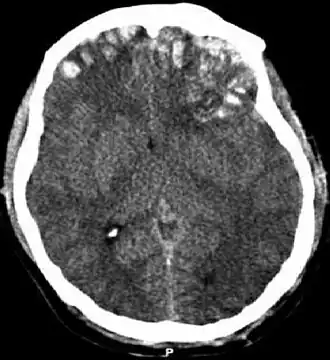

Un scanner crânien devra être fait en urgence en cas d'un déficit de la conscience, même transitoire ou de survenue secondaire, en cas de déficit neurologique (baisse de la mobilité d'un membre, troubles de la parole, amnésie), au moindre doute sur une fracture crânienne, en cas de survenue de crise convulsive ou en cas de vomissements[17]. Chez l'enfant, l'indication d'un scanner est d'autant plus grande qu'il est jeune.

Le scanner cérébral permet de voir l'étendue des lésions : présence d'une fracture, taille et localisation d'un hématome, conséquences sur les ventricules cérébraux, présence ou non d'un œdème cérébral. Une admission en unité de réanimation ou en soins intensifs de neurochirurgie est nécessaire. L'utilisation systématique d'une perfusion hypertonique dans le but de limiter l'œdème cérébrale a une efficacité discutée[22], de même qu'une ventilation hyperoxique (avec plus d'oxygène que de besoin)[23]. Toutefois, la mise sous ventilation artificielle est très souvent nécessaire. L'intérêt de la mise sous hypothermie est également incertain[23].